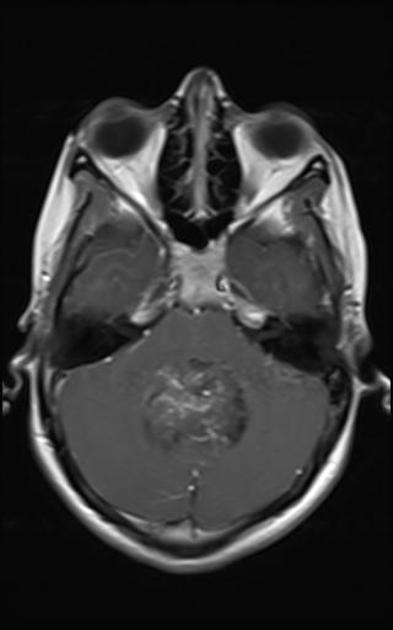

A comprehensive history and physical and MRI imaging of the CNS axis is required. The MRI typically shows a posterior fossa mass which is hypointense to iso-intense on T1 series. It is hyperintense (white) to white matter on T2 series. T1/gad shows heterogeneous enhancement and CT shows calcifications. Once the imaging series is obtained, CSF sampling (particularly in anaplastic Grade III) should be obtained to rule out leptomeningeal seeding. CSI may be required in anaplastic ependymoma.

Ependymoma T1 no contrast

Ependymoma T1 gad